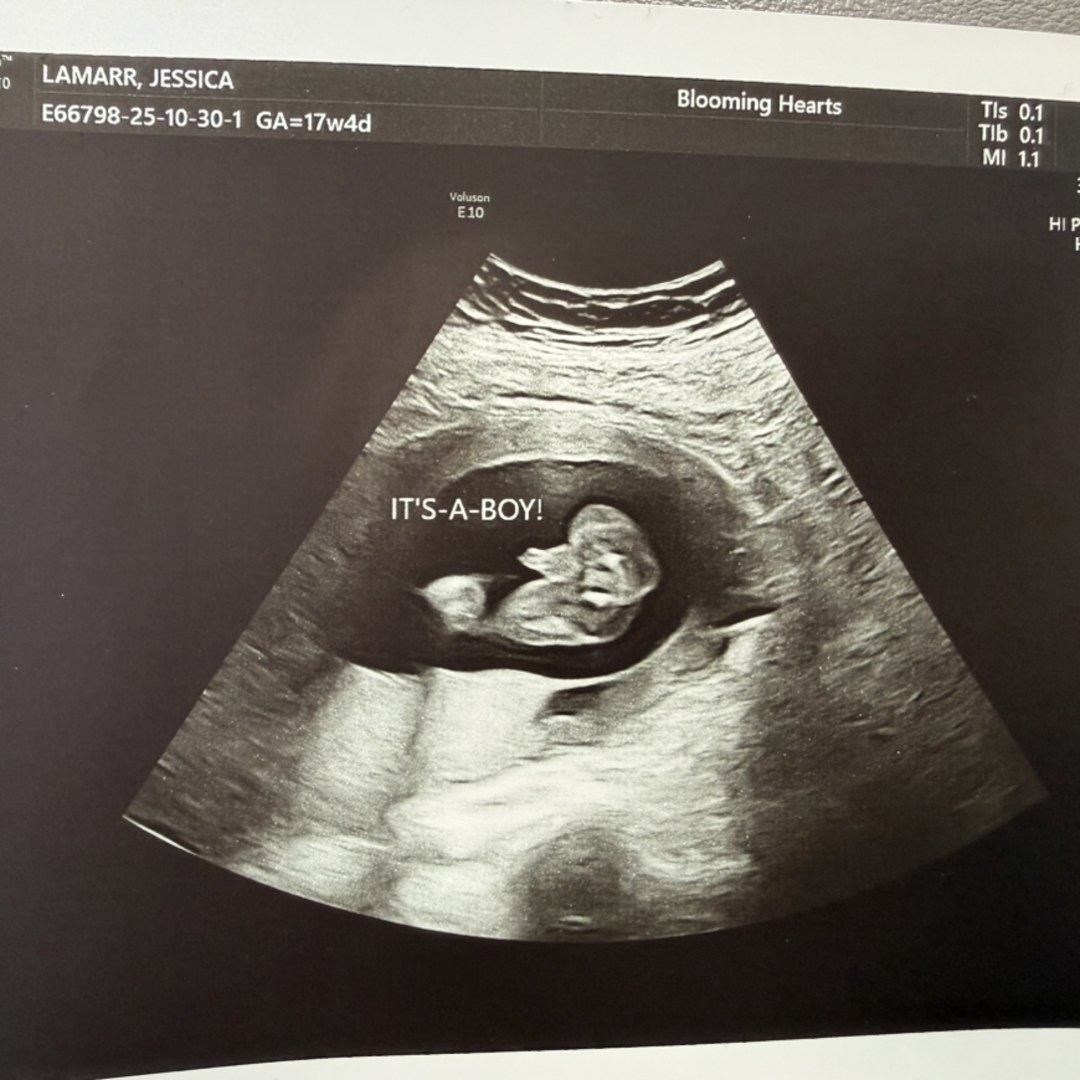

Jessica and Jared’s Baby Registry

Jessica & Jared LaMarr

We are so excited to add baby brother to our family, we can’t wait for you all to meet our sweet boy! 💙